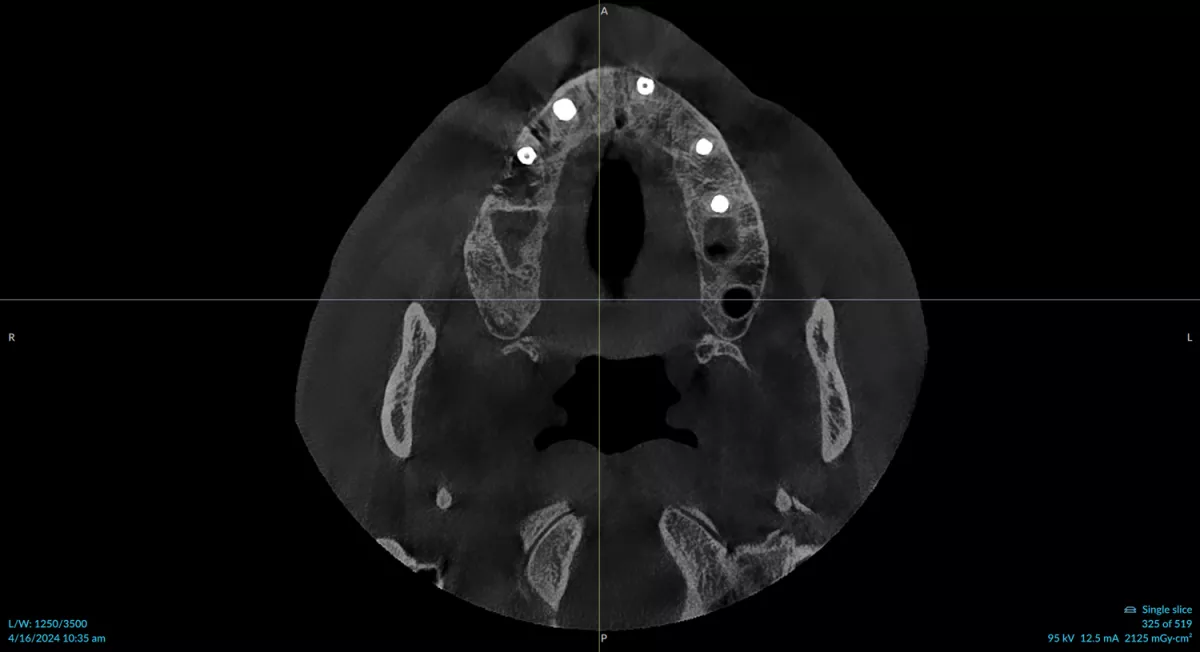

Help your staff capture what you truly need to see in your diagnostic images with a wide range of customizable field of view (FOV) options ranging from 5 x 5 cm to 10 x 15 cm* and adjustable volume height with low dose, standard, endo and high resolutions.

With 6 preset FOVs and 66 customizable volume sizes, you can achieve optimal diagnostic output at the lowest reasonable dose.

Gain greater insights into root anatomy, proximity to critical structures, implant visualization and osseointegration. Diagnostic efficacy can lead to predictable outcomes.

The OP 3D EX and DTX Studio Clinic enable you to expand your clinical applications, by allowing for multiple views of your patient scans, presurgical assessments of anatomy, and supporting the placement of accurate and precise implants.